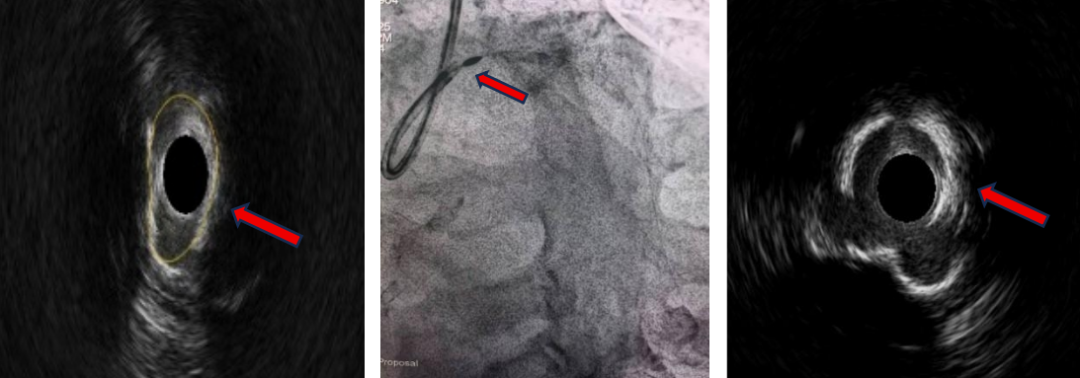

术中血管内超声图像及旋磨,可见白色钙化环被磨薄、管腔扩大,钙化环松解